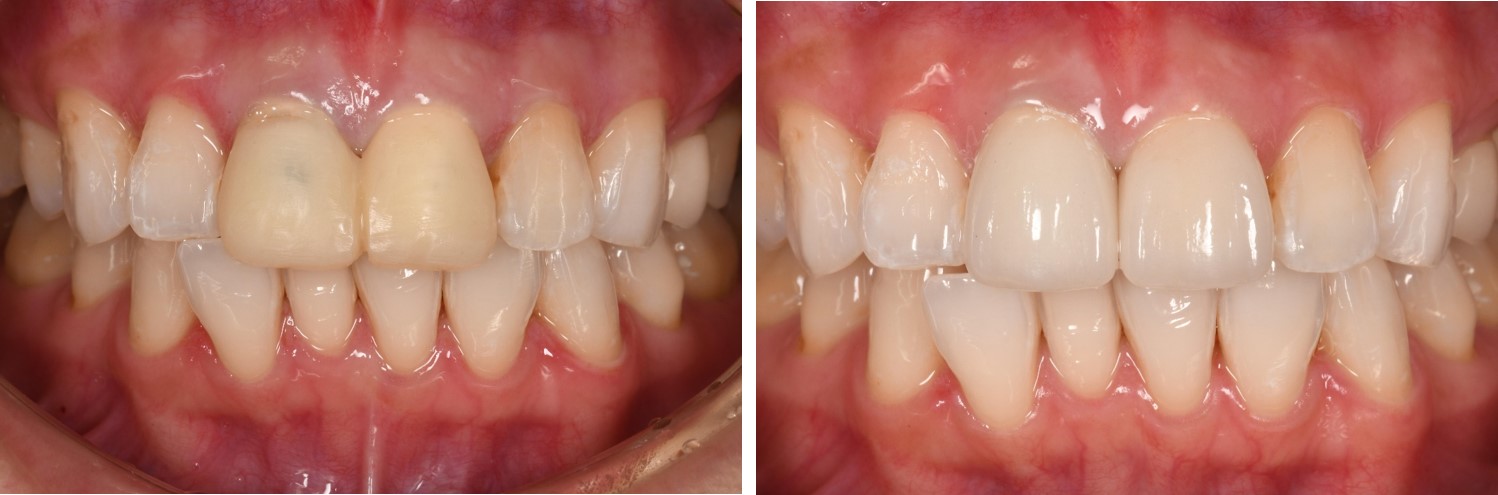

術前、術後比較

初診口內照,前牙美觀不良

治療後口內照